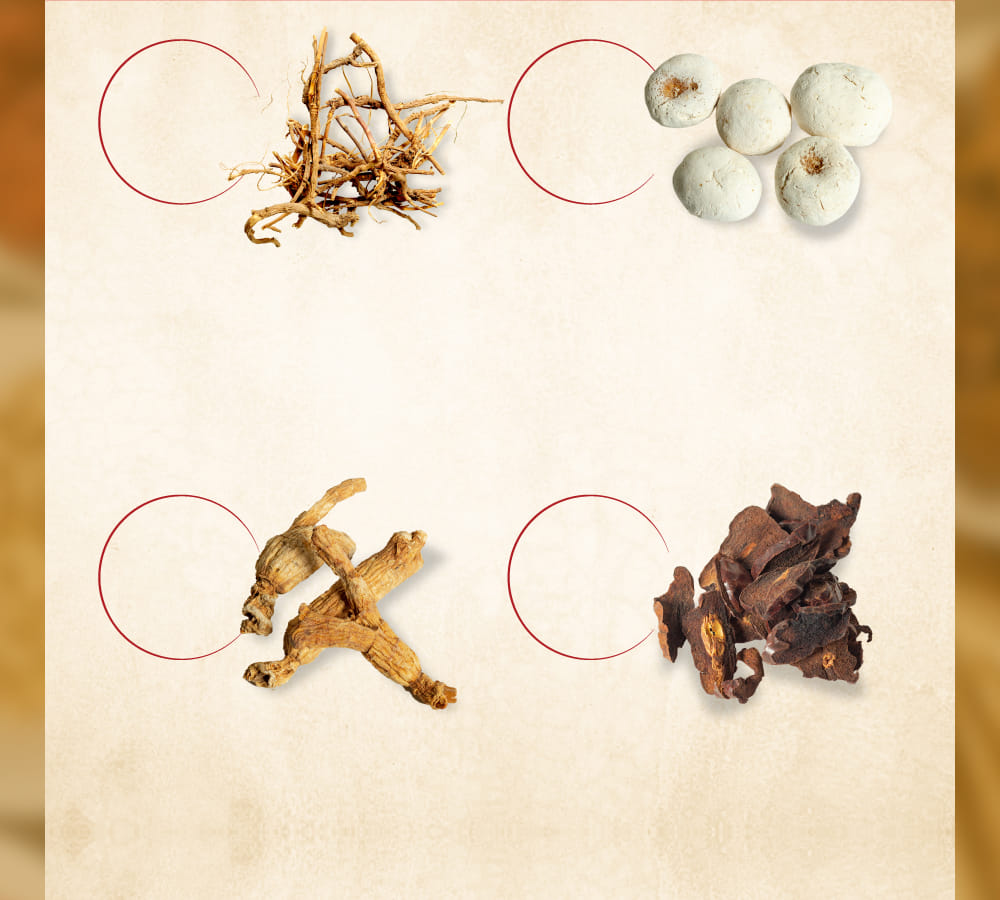

サイコ

セリ科ミシマサイコの根を

乾燥させたもの

効能・効果

消炎・鎮痛作用

ハンゲ

サトイモ科カラスビシャクの

コルク層を

取り除いた

塊茎を乾燥したもの

効能・効果

消化不良改善作用

オウゴン

シソ科のミコガネハナの

根の周皮を除去したもの

効能・効果

解熱・消炎・解毒作用

タイソウ

クロウメモドキ科

のナツメの

成熟した果実を

乾燥させたもの

効能・効果

鎮静・鎮痛作用

ニンジン

オタネニンジンウコギ科の

細根を除いた根を

乾燥したもの

効能・効果

消化促進作用

ショウキョウ

ショウガの根茎を乾燥し、

周皮を除いたもの

効能・効果

抗炎症・消化促進作用